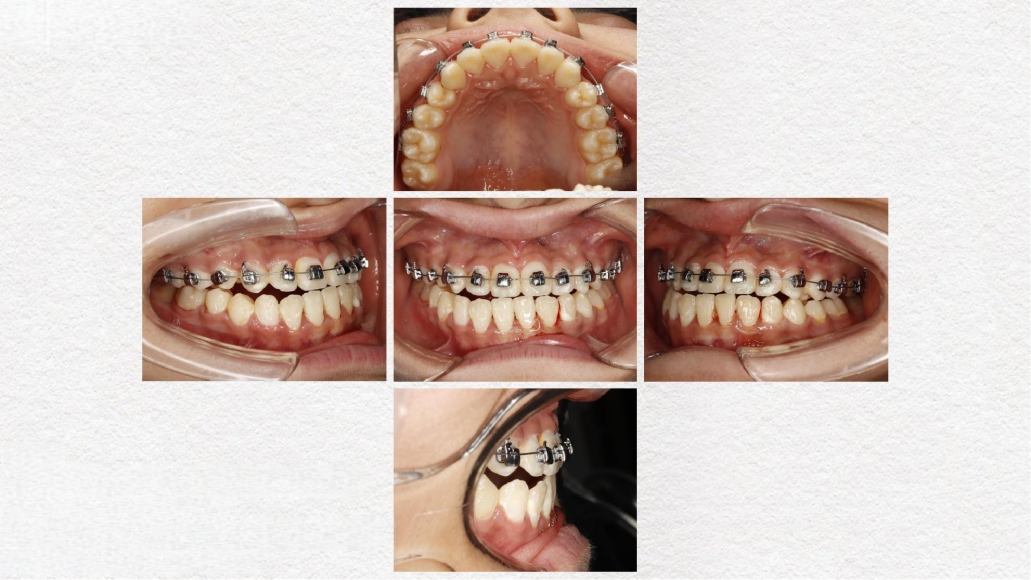

临床案例